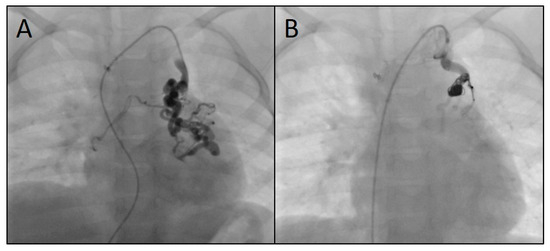

2.2. Catheterization and Transcatheter Embolization